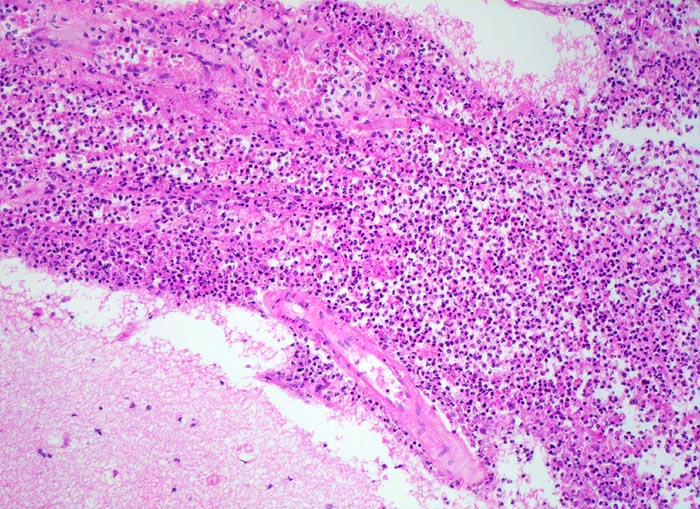

PathoPic – image database / PathoPic ID 5189 - Eitrige Leptomeningitis

Eitrige Leptomeningitis

Entzündung infektiös

Meningen

Nervensystem

Bronchopneumonie. Nachweis von Pneumokokken im Abstrich von der Hirnoberfläche und von der Lunge.

Kopfschmerzen seit 3 Tagen mit zunehmender Bewusstseinseintrübung, Fieber. Diabetes mellitus. Patientin stirbt kurz nach Spitaleintritt.

Histologie

100